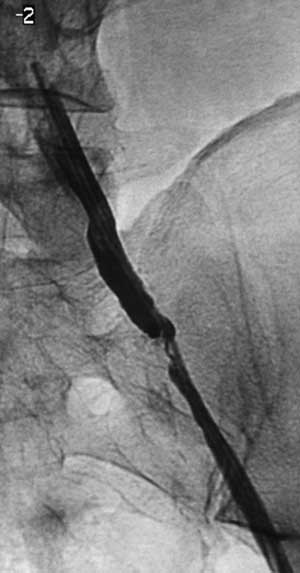

Имплантация артериального стента Белорусского производства.

Рис. 2. Сегментарные стенозы подвздошных артерий, критический стеноз левой наружной подвздошной, окклюзия левой внутренней подвздошной артерий.